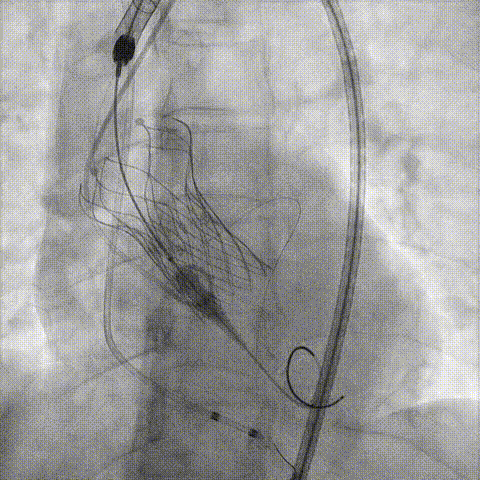

预置Telescope™导引延长导管及导丝保护左冠,

18mm球囊预扩张再次评估冠脉闭塞风险。

Telescope™+Runthrough

18mm*40mm 预扩张

预埋 Resolute Integrity 3.5*26mm

再次评估左冠开口